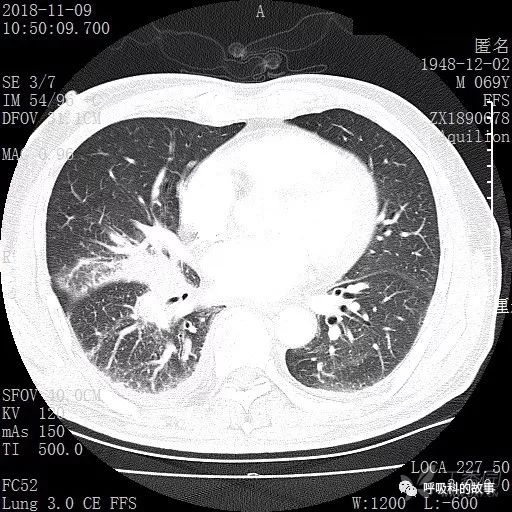

胸部增强CT示右肺门占位伴远端阻塞性肺炎,纵膈、右肺门、右侧颈根部、右侧腋下及肝门部肿大淋巴结。两侧胸腔少量积液。

纵隔窗的增强CT

肺窗CT